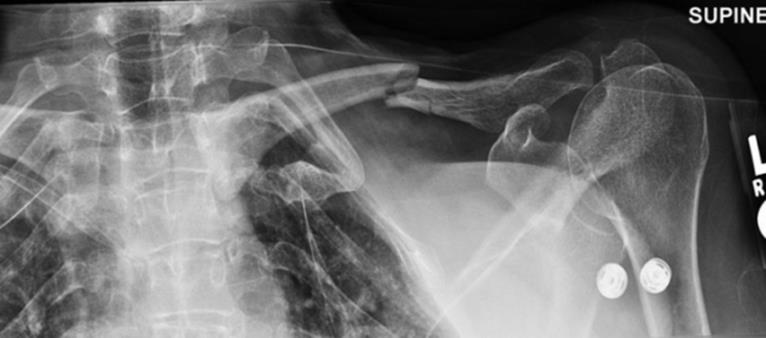

o Perform an AP (Figure 2.1A) and a lateral projection (axillary lateral or scapular Y-view) (Figure 2.1B)

Figure 2.1A and 2.1B Radiographs of a posterior shoulder dislocation.

A: An AP projection is shown with no obvious dislocation.

B: A lateral projection (scapular Y-view) for the same patient shows the humeral head to be dislocated posteriorly. (Reproduced with permission of the Department of Emergency Medicine, Feinberg School of Medicine, Northwestern University.)